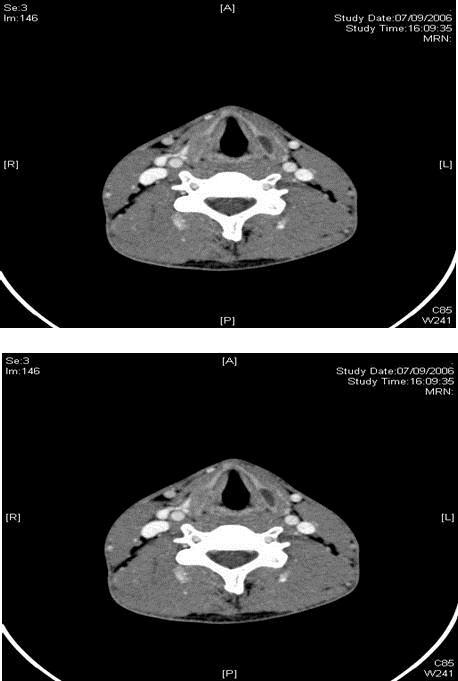

We report a case of a 19 year old gentleman with no significant past medical or family history of note, who first presented with right-sided headache of 1 month duration. CT scan showed focal bony thickening involving the right squamous temporal bone and greater wing of the sphenoid with internal ground-glass appearance, consistent with focal fibrous dysplasia. He re-presented 5 months later with right-sided cervical lymphadenopathy of 1-month duration. Fine needle aspiration cytology showed necrosis with mild acute inflammation. CT scan revealed right-sided suppurative cervical lymph nodes at levels 2 and 3, with an incidental finding of bilateral lamella expansions of the thyroid cartilage with cystic changes on the left, consistent with fibrous dysplasia. Cultures from the aspirate were positive for mycobacterium tuberculosis and the patient was treated with 6 months of anti-tuberculous chemotherapy. He has been followed-up for a 3 year duration, and has since remained well, with no further complaints of headache, neck pain or swelling.

Figure 1.CT scan showing bilateral lamella expansions of the thyroid cartilage with cystic changes on the left